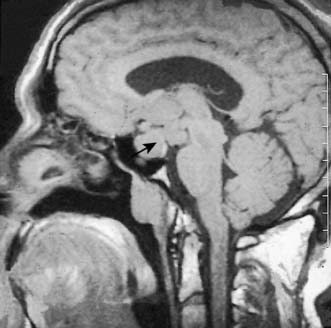

Functioning pituitary adenomas may result from over-stimulation by hypothalamic factors. Initially small and confined within the gland (microadenomas), they grow slowly and can ultimately expand the sella turcica. Eccentric enlargement is common. Upward extension of the adenoma may stretch the diaphragm or herniate through it, to compress the optic chiasma and cause visual defects. It is therefore important that pituitary adenomas are detected before they enlarge the fossa or extend above it. CT with contrast enhancement and MRI (Fig. 20.12) are used to image the tumour. Three endocrine syndromes caused by anterior pituitary disorders have surgical relevance.

Surgical hypophysectomy